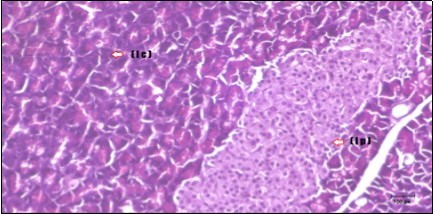

Histological examination of pancreas of the control rats showed normal sized islets of pancreas (Ip) compared to the diabetic rats which showed markedly atrophic islets of pancreas (I.p.) (Figure 8 and Figure 9). Pancreas of in groups (3) and (4) rats showed mild atrophic islets of pancreas (I.p.) with inflammatory cellular infiltrate (Figure 10 and Figure 11). The pancreas of rats in group (5) showed nearly normal islets of pancreas (I.p.) with few inflammatory cellular infiltrate (I.c.) (Figure 12).

Figure 12.Photomicrogragh of pancreas section of treated rat with both Fenugreek and Glimepiride showing nearly normal islets of Langerhans with spindle (arrow) & polygonal cells (dashed- arrow). (H&E) (40x).

Photomicrogragh of pancreas section of treated rat with both Fenugreek and Glimepiride showing nearly normal islets of Langerhans with spindle (arrow) & polygonal cells (dashed- arrow). (H&E) (40x).

Histopathological observation in diabetic control showed degenerative changes in both endocrine and exocrine pancreases. A probable explanation may be related to oxidative stress resulting from hyperglycemia which decreases the antioxidants levels and increases ROS 33 and the activities of antioxidant enzyme were altered in diabetic rats. These effects further exacerbate the development and progression of diabetes complications and these may represent the causes of degeneration revealed in histological sections. Fenugreek improved blood glucose levels and insulin, lowered pancreatic islet and β-cells damage which may be attributed to its immune modulatory activity and insulin stimulation action along with its antioxidant potential 32. Glimepiride caused restoration of morphology of beta cell of diabetic and it increased percentage of beta cells 34. This protective effect could be attributed to the antioxidant properties of Glimepiride. Combination therapy improves the protective effect of both therapies alone.